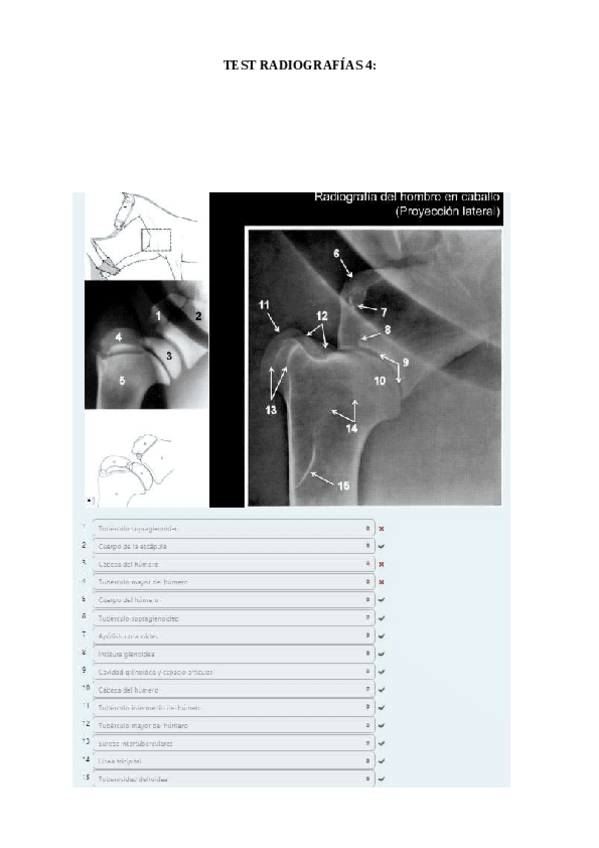

He publicado nuevos apuntes de 1º EMBRIOLOGÍA Y ANATOMÍA I: TEST-4-Radiografias-corregido.pdf

10 páginas